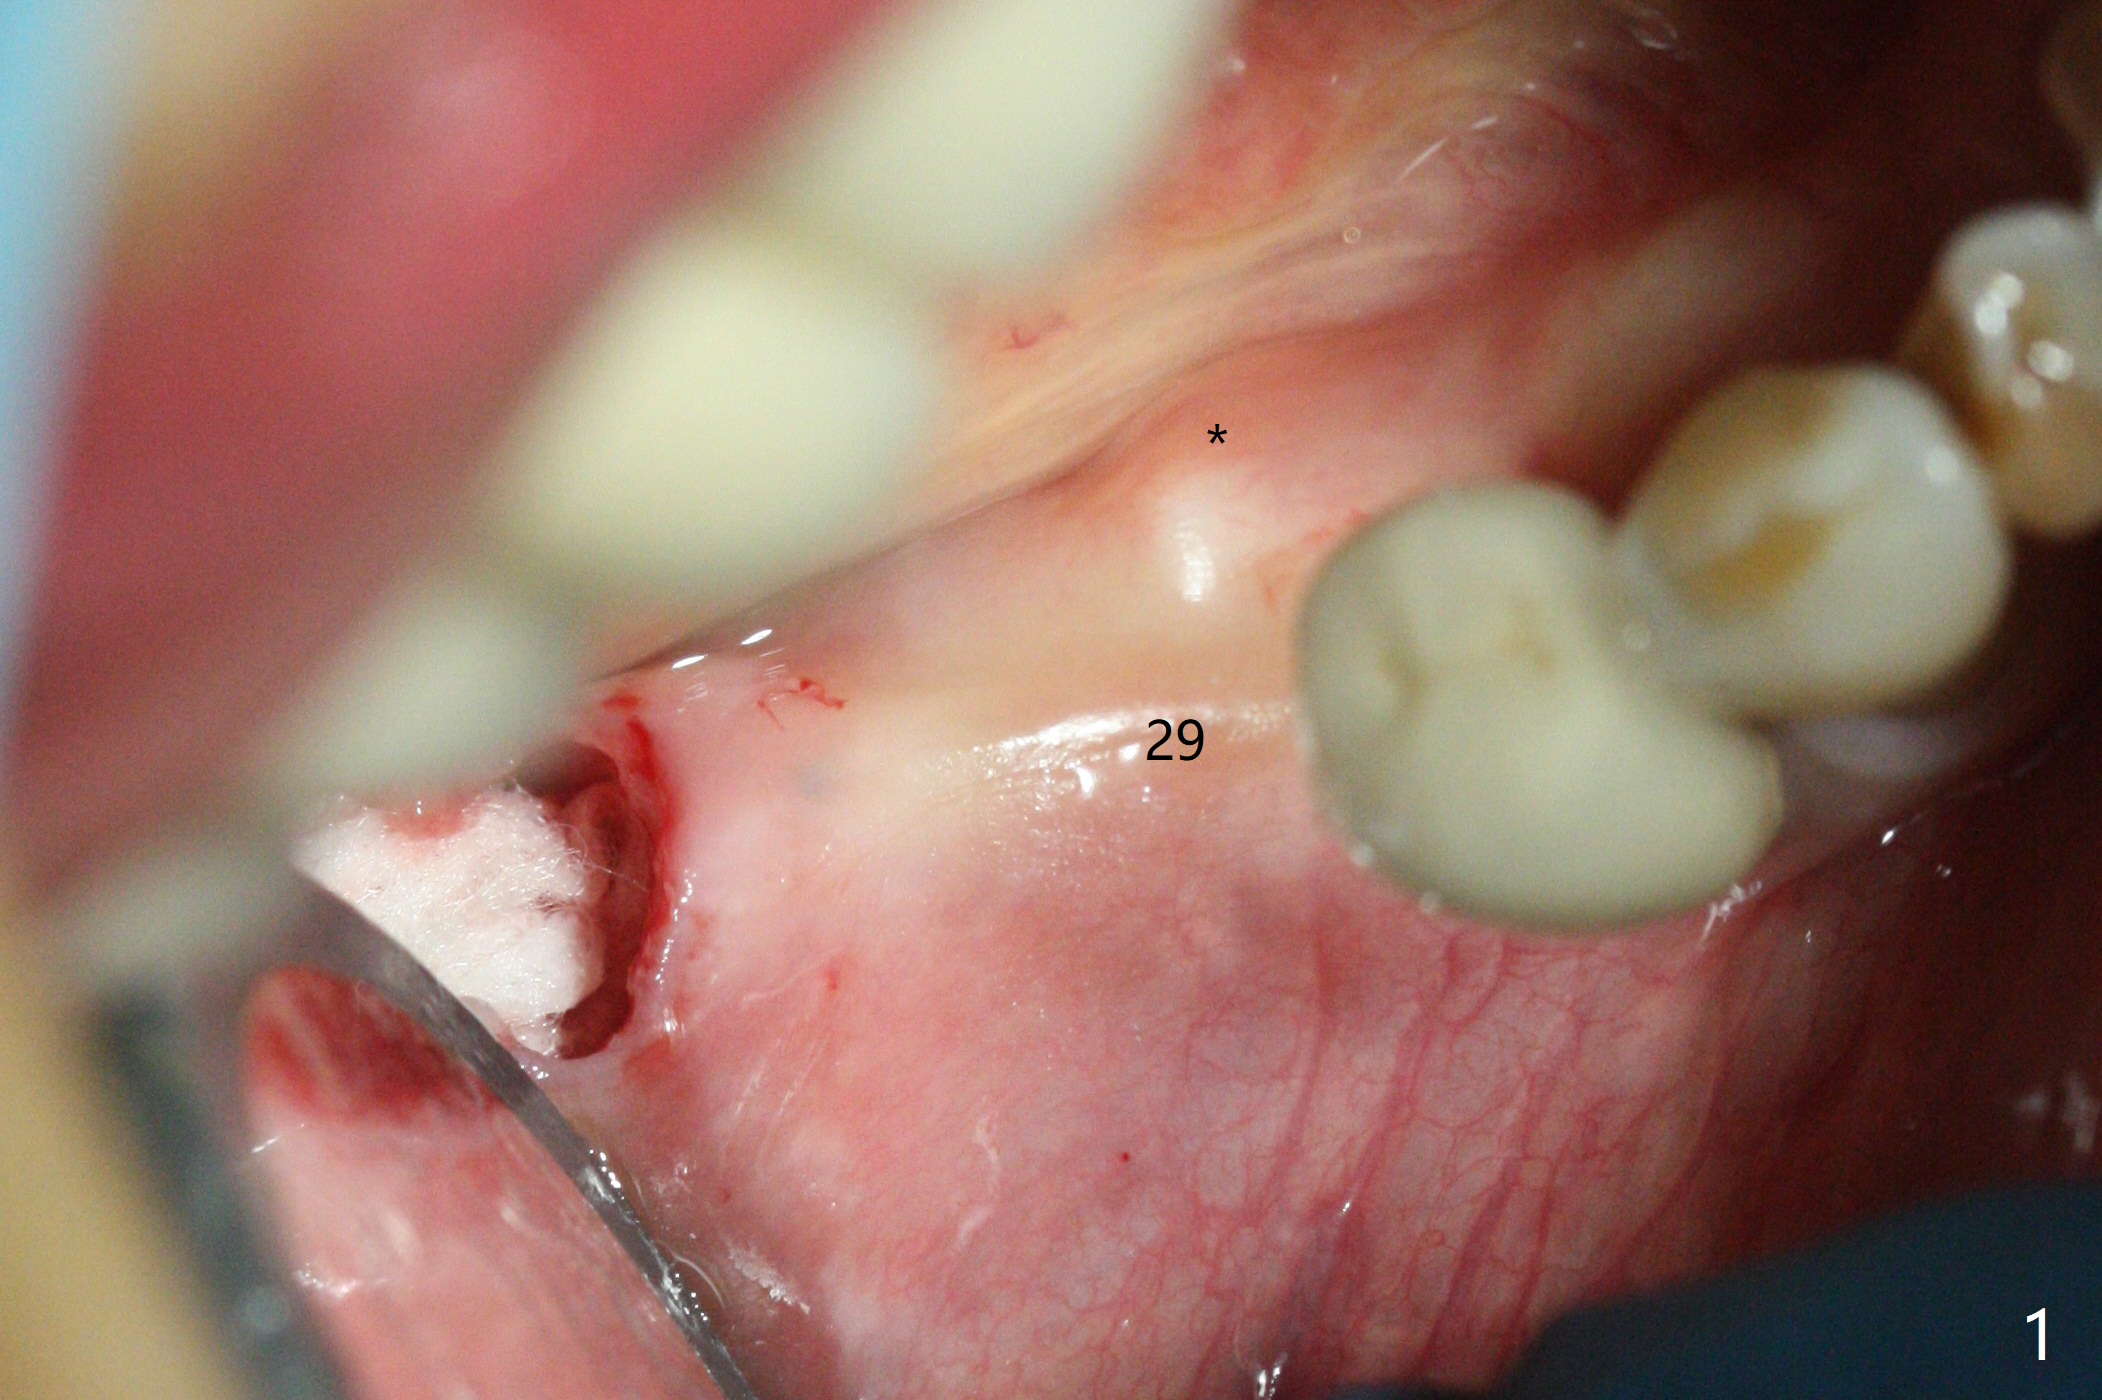

The keratinized gingiva at #29 is slightly lingual with torus mandibularis (Fig.1 *). 4 mm tissue punch through metal sleeve makes a superficial mark (Fig.4). To save the keratinized tissue, a lingual flap is designed as shown in Fig.4 insert (black line; avoiding the torus *). Osteotomy involving 4 mm cortical drill is related to <10 Ncm insertion torque of a 4x11 mm implant; a healing screw is placed (Fig.5 S). After removing the torus and placement of bone graft and collagen plug (Fig.6 *), the lingual flap is sutured in place without tension because of the torus resection (Fig.7 *). Later the wound is covered by periodontal dressing.

The extraction socket of #31 has a thin septum (Fig.2), which is removed partially with 12 mm bone trimmer (Fig.3). After placement of a 5x9 mm FC implant (~40 Ncm) and 6 mm bone profile drill, a 5.5x4(2) mm abutment is incompletely seated (Fig.5 <) and later is changed to a 4.5x1 mm temporary abutment (Fig.6, 8 T). The latter is used to fabricate a provisional, which in turn supports the distal papilla (Fig.8 *). The gingiva is slightly erythematous immediately post periodontal dressing removal (3 weeks postop, Fig.9). Take CT to confirm whether the cortical drill helps keep the #29 implant lingual. Use a profile drill at #29 if crestal bone loss is not obvious. There is bone coronal to #29 implant 4 months postop (Fig.10). Upon incision, the ridge is rounded (Fig.10'), but the implant appears to be buccally placed (Fig.10'' (post high speed handpiece and 5.5 mm profile drill)). The latter is confirmed by CT (Fig.12, as compared to design (Fig.11)). In spite of use of cortical drill coronally, the implant is still deviated buccally due to contrasting deferential bone density linguobuccally (Fig.13). By comparison, there is no such bone density differential involving an immediate implant at #31; the implant is placed in the socket without contacting the buccal or lingual cortices (Fig.14). The final implant is the same as expected (Fig.15). To avoid implant deviation in the lower premolar region, leave the root in place until osteotomy is finished. Five months postop, the temporary and healing abutments at #31 and 29 change to pair ones (Fig.16). Since there is limited clearance from the crestal bone, smaller abutments are used with the apparently same degree of seating (Fig.17). The abutments are prepared due to the mesial (#31) and buccal (29) tilt before impression.